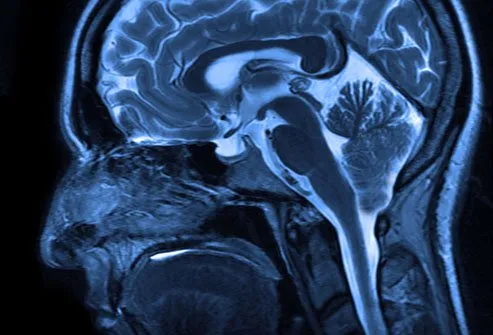

A diagnosis of Chiari malformation can be a scary and confusing time for patients. This condition occurs when the cerebellum, located at the base of the brain, extends into the spinal canal. This puts pressure on both the brainstem and spinal cord, leading to a range of symptoms such as headaches, neck pain, numbness in extremities, dizziness, or balance issues.

Diagnosis often begins with a physical exam to assess symptoms and medical history. Imaging tests such as MRI or CT scans may also be ordered to examine the brain and spine for abnormalities. A neurologist or neurosurgeon will then review these results to confirm whether Chiari malformation is present.